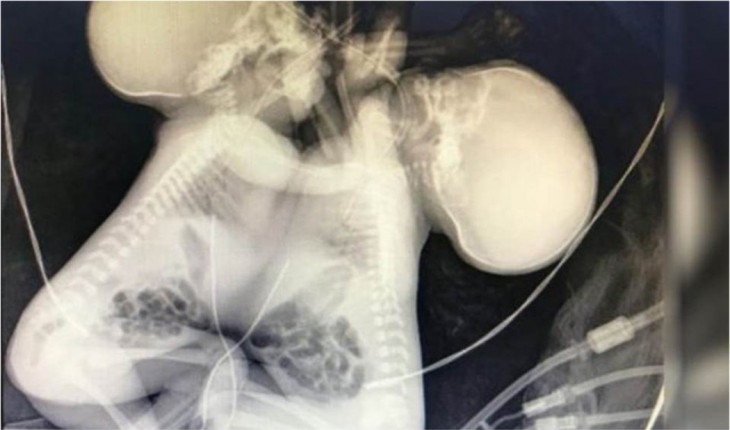

A criança e a mãe passam bem, mas o bebê precisará ser submetido à alguns exames.

O médico responsável pelo caso revelou o motivo de não poder realizar uma cirurgia para separá-las.